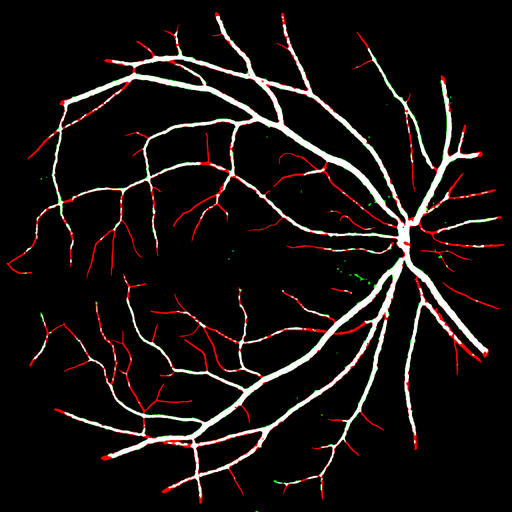

FIVES Refer to caption Refer to caption Refer to caption Refer to caption Refer to caption Refer to caption Refer to caption

OCTA_3M Refer to caption Refer to caption Refer to caption Refer to caption Refer to caption Refer to caption Refer to caption

LEAF Refer to caption Refer to caption Refer to caption Refer to caption Refer to caption Refer to caption Refer to caption

CRACK Refer to caption Refer to caption Refer to caption Refer to caption Refer to caption Refer to caption Refer to caption

SCRATCH Refer to caption Refer to caption Refer to caption Refer to caption Refer to caption Refer to caption Refer to caption

SOIL Refer to caption Refer to caption Refer to caption Refer to caption Refer to caption Refer to caption Refer to caption

Input UNet++ [14] CSSR [8] FR-UNet [15] HQ-SAM [25] Rein [42] Ours

Figure 8: Qualitative comparison of UCS with other methods across datasets from diverse domains. The left text identifies the image dataset, while the bottom text denotes the segmentation model used. The results are presented as pixel-level comparisons with the ground truth, where black, white, red, and green pixels represent true negatives (TN), true positives (TP), false negatives (FN), and false positives (FP), respectively.

Fig. 8 presents a visual comparison of segmentation results across a range of datasets. In the FIVES dataset, our method clearly outperforms others, exhibiting precise delineation of vascular structures with minimal red (false negatives) and green (false positives) pixels. In the LEAF dataset, our approach segments the delicate vein patterns, while other methods produce incomplete or fragmented results, primarily showing red pixels indicating significant false negatives. In the SOIL dataset, other methods exhibit significant noise and incomplete segmentation. Our method provides a complete and clean segmentation. Overall, the proposed UCS consistently outperforms competing methods by delivering higher true positive rates, lower false positives, and superior structural coherence across all examined domains.